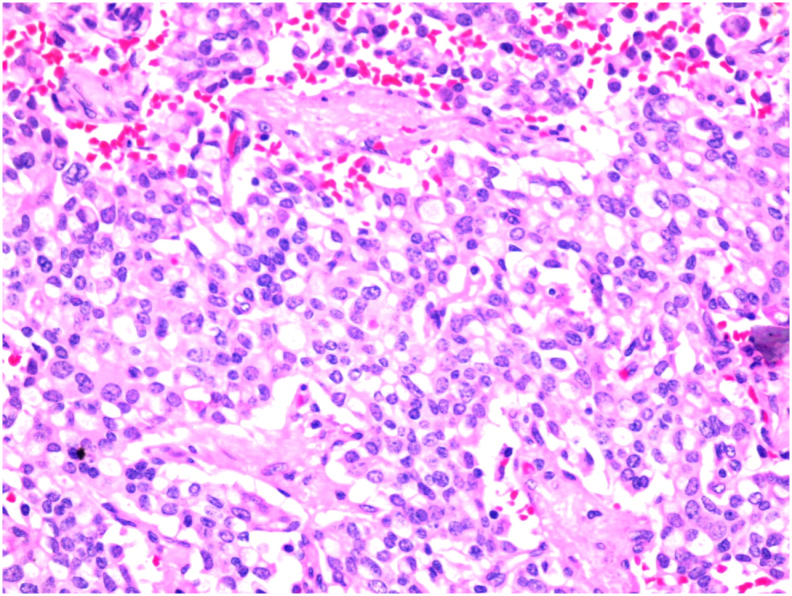

The pathology [Fig. 4, Fig. 5] showed a proliferation of pleomorphic round to oval cells with a moderate amount of finely granular cytoplasm. The nuclei show a salt and pepper appearance. The mitotic index is less than 1mitosis/10HPF. The tumor cells are invading the mucosa of the common bile duct and the surrounding fat. Perineural invasion and lymphovascular invasion are seen. Chromogranin and Synaptophysin immunohistochemical stains were done, and they were positive in the appearing neuroendocrine cells and the signet appearing cells. Ki67 immunohistochemical stain was positive in less than 2% of the tumor suggestive of well-differentiated neuroendocrine carcinoma, grade 1.